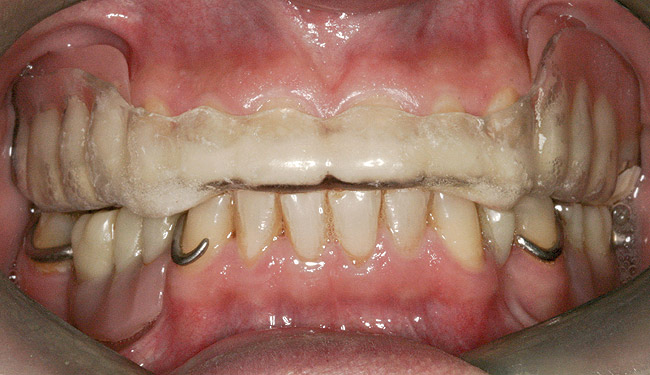

Figure 2  Intraoral occlusal view of maxillary dentition with the existing removable prosthesis presenting excessive signs of wear.

Figure 2

Initial examination revealed a partial edentulous patient with extensive wear of the maxillary anterior teeth and moderate wear in the mandibular teeth (Figure 1, Figure 2, Figure 3 , Figure 4, Figure 5, Figure 6 and Figure 7). The patient's maxillary and mandibular RPDs also showed excessive wear and multiple signs of fractures (Figure 2 and Figure 3). The patient had been wearing a mandibular nightguard for 8 years.